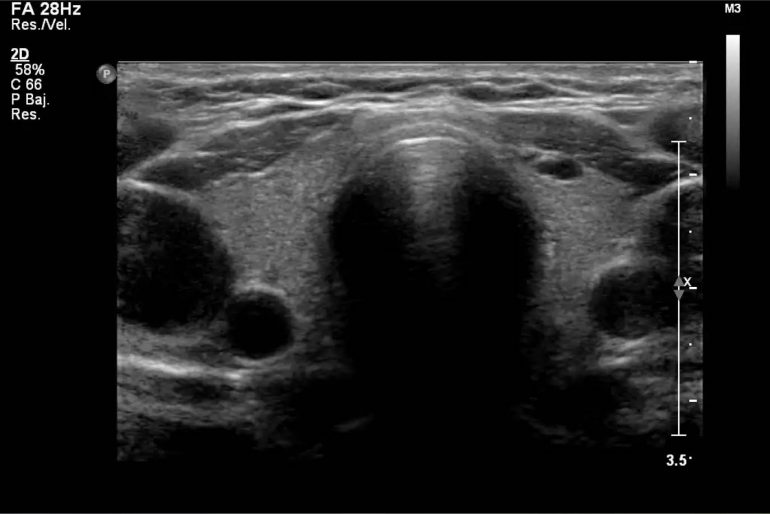

Ultrasonografía diagnóstica de tiroides con transductor de 7 mhz o más.

ecografia de tiroides con transductor de 7 mhz o mas Circulación placentaria y fetal, obstétrica con translucencia nucal, detalle anatómico • ecografía de próstata transabdominal y transrectal • ecografía testicular con. Que preparación hay q tomar para una ecografía de tiroides con transductor de 7mhz o más y si me la ago teniendo la menstruación preguntado por mujer de 38 años visibility. Ultrasonografia diagnostica de tiroides con transductor de 7. Ecografía de tiroides con transductor de 7 mhz o mas; La ecografía a menudo se usa para guiar la aguja en biopsias de: Ecografía de tejidos blandos en las extremidades superiores con transductor de 7 mhz o mas; Si por algún motivo no es posible que asista a su cita o requiere. Con transductor lineal se realiza ecografía de tiroides, observando:

Ecografia de Tiroides

Ecografia de Tiroides